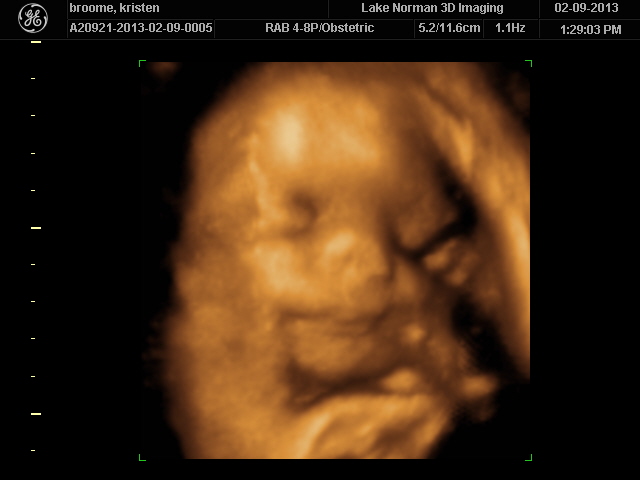

..We meet again, little boy!